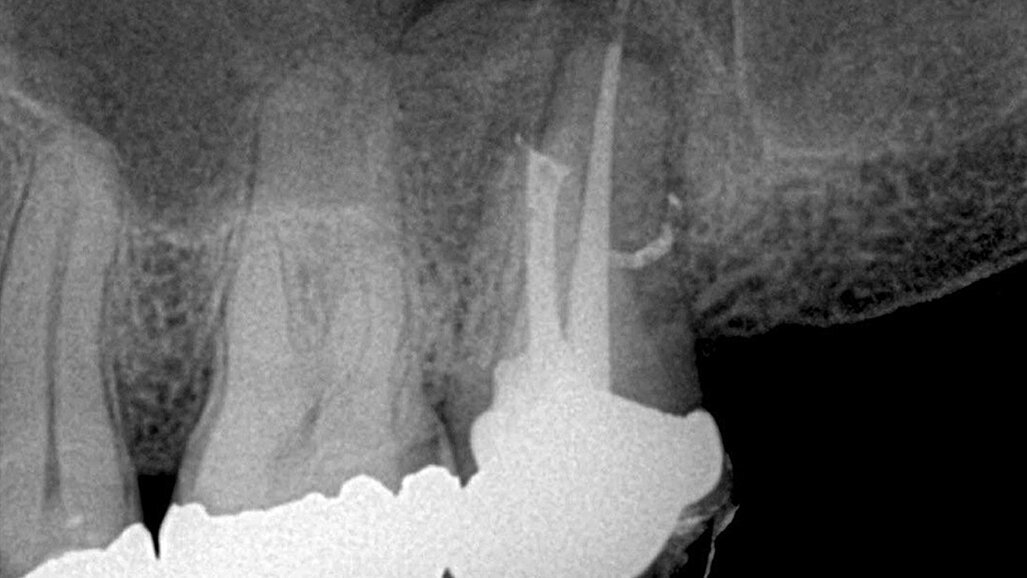

Slika 3: Nekrotičan/zaražen zub: donji premolar pacijenta koji se žali na konstantan, pulsirajući bol. Infekcija nije ograničena samo na apikalni deo već je takođe locirana i u srednjem delu lateralnog kanala. Postoperativni rendgenski snimak pokazuje 3-D zaptivanje apikalne regije sa svim anastomozama lateralnog i pomoćnih kanala.

Slika 4:Kompleksnost apikalne regije pokazana nakon hemijske obrade kanala, sušenja i zaptivanja tehnikom vertikalne kondenzacije.

Slika 5:Prikazuje slučaj pogodan za reviziju punjenja s obzirom na loš rezulatat prethodne terapije kanala korena. Uz odgovarajuću obradu i irigaciju(Sleimanova faza) i zahvaljujući teškoj ali uspešnoj potrazi za distalnim kanalom, izvršena je 3-D opturacija kanala koja pokazuje suženje između mezijalnog i distalnog kanala kao i veoma visoko postavljene lateralne kanaliće u palatinalnom kanalu.

Slika 6:Vitalni prvi gornji molar sa ireverzibilnim pulpitisom. Uočljiv je izrazito dugačak palatinalni kanal (oko 31mm),koji je ipak zapečaćen zajedno sa petljom lateralnog kanalom zahvaljujući dobroj hemijskoj obradi kanala koja je omogućila kompaktnost punjenja.

Slika 7: Neuspešan tretman kanala korena sa apikalnom infekcijom i internom resorpcijom u apikalnom delu.

Slika 8: Kontrolna slika pokazuje brzo zarastanje i apikalne regije i resorptivne lezije.

Na slikama iznad predstavljamo neke od tipičnih slučajeva koji pokazuju postignutu čistoću kanala korenskog sistema prikazom bočnih i / ili pomoćnih kanala vidljivih zahvaljujući 3-D vertikalnoj kondenzaciji (Slika 3-6).

Slučaj neuspešnog tretmana korenskog kanala sa apikalnom infekcijom i unutrašnjom resorpcijom u predelu apeksa prikazuje slika iznad (Slika 7). Nakon uklanjanja prethodnog punjenja, izvršena je hemijska priprema, uz pomoc parcijalnog vakuuma unutar sistema hemikalije su mogle očistiti područje resorpcije bez agresivnog dejstva na periodontalni ligament; ovo je dovelo do zaista trodimenzionalne obturacije sistema kanala.

Slika nakon 4 meseca potvrdjuje brzo zarastanje i apikalne regije i područje resorptivne lezije.